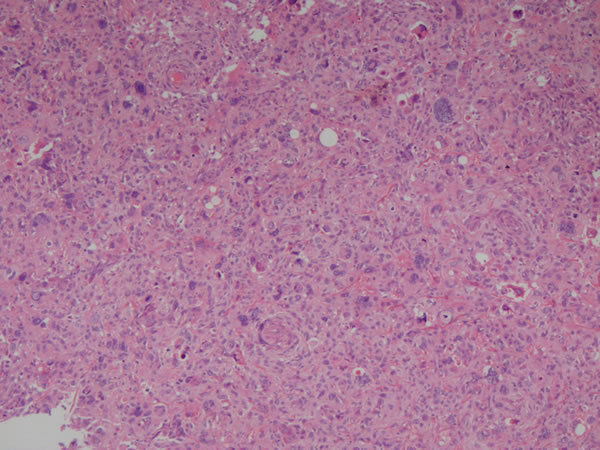

Não é possível id. - células indiferenciadas Anaplasia - tumor maligno indiferenciado |

| Não é possívei id - Células pleomórficas, mitoses atípicas, vasos, áreas de necrose, células com citoplasma escasso e núcleos grandes, hipercromasia nuclear Neoplasia maligna indiferenciada | |